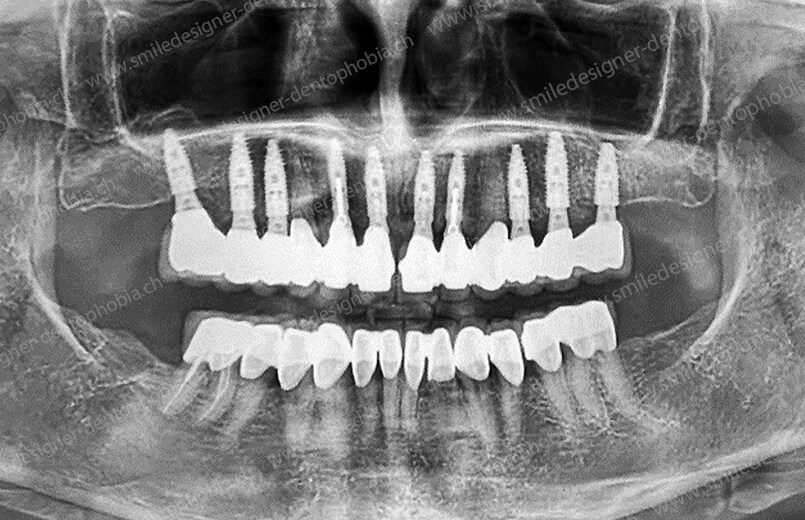

Cas clinique « GOLD STANDARD MCI » bi-maxillaire : Bridge implanto-porté sans extension postérieure (ALL ON 10). Version définitive des bridges avec un cosmétique en céramique.

Cas clinique « GOLD STANDARD MCI » bi-maxillaire : Bridge implanto-porté sans extension (ALL ON 10). Version définitive des bridges avec un cosmétique en céramique.